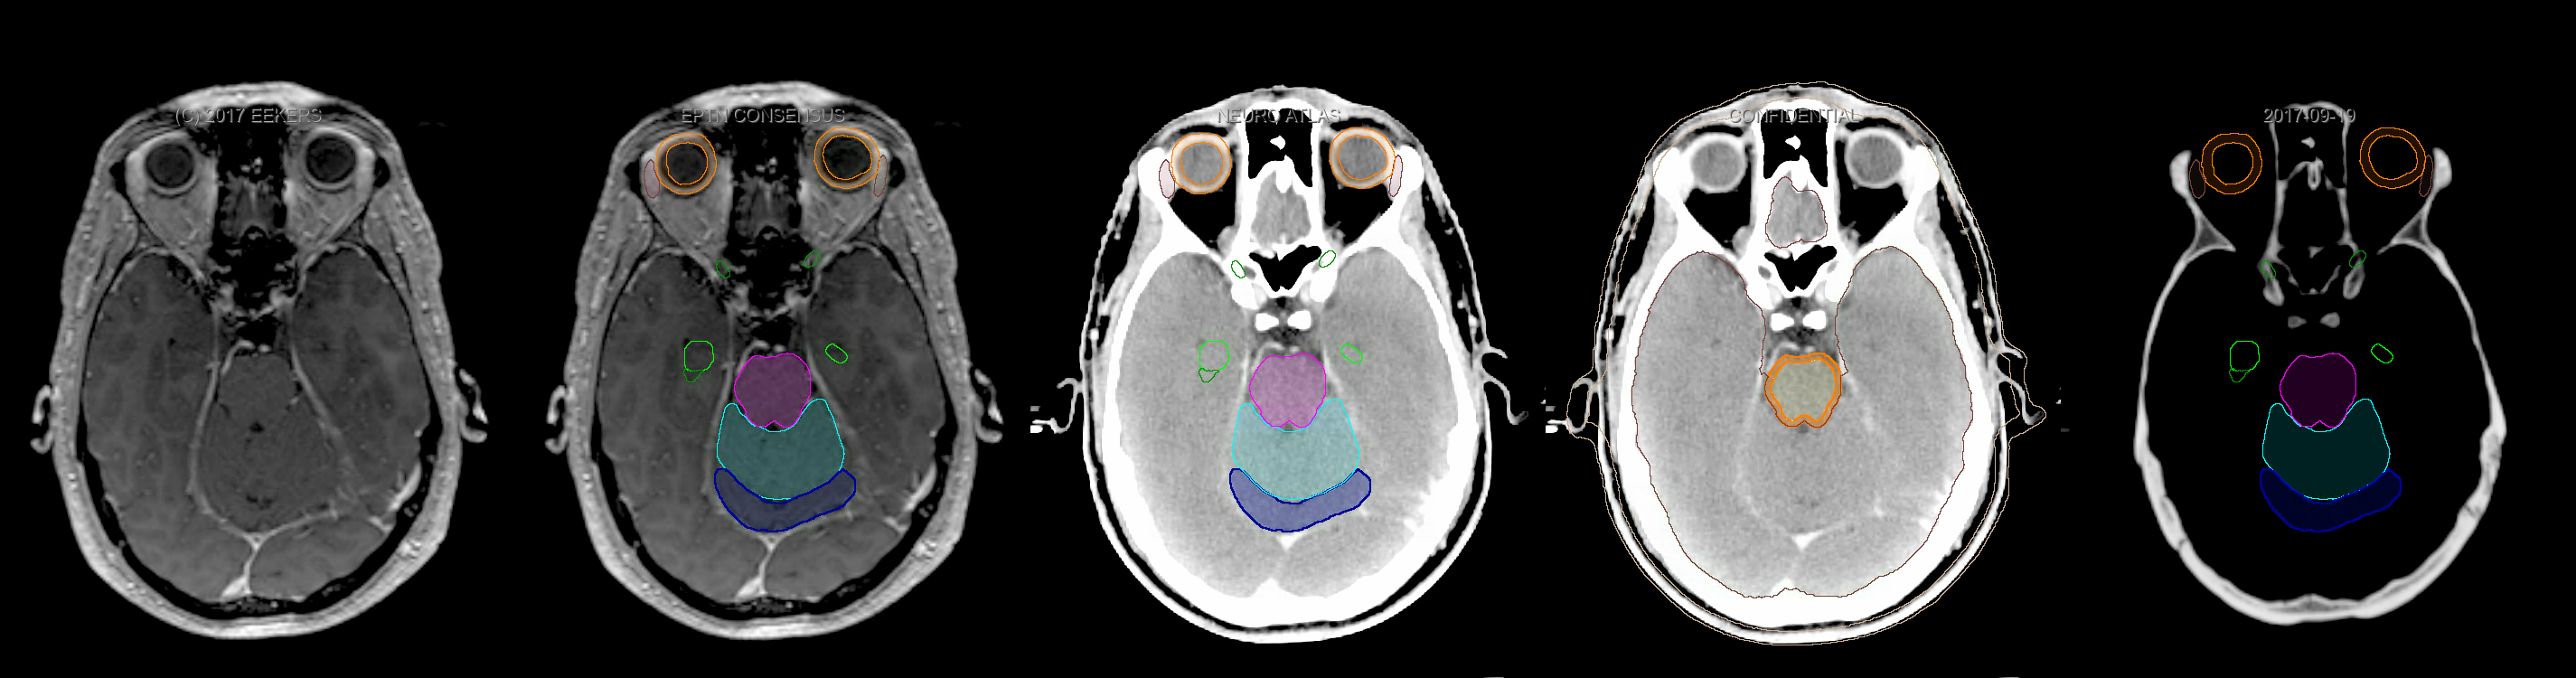

Eekers et al. have published an international neurological atlas for contouring of organs at risk in consensus with the European Particle Therapy Network (EPTN). The purpose of this consensus atlas is to decrease inter- and intra-observer variability in delineating OARs relevant for neuro-oncology. We propose this atlas is used in photon and particle therapy in order to derive consistent dosimetric data. When required this atlas will be updated according to new insights.

Included are all OARs known to be relevant for radiation-induced toxicity in neuro-oncology: brain, brainstem, cochlea, vestibulum & semicircular canals, cornea, lens, retina, lacrimal gland, optic nerve, chiasm, pituitary, hippocampus and skin. A new OAR relevant for neuro-cognition, the posterior cerebellum is also included.

Three-dimensional delineation of the fifteen consensus OARs for neuro-oncology are shown on CT and 3 Tesla (3T) MR images (slice thickness 1 mm with intravenous contrast agent). All are presented in transversal, sagittal and coronal view.

From left to right: MR without structures, MR with structures, CT (WW/WL 120/40) with structures, CT (WW/WL 120/40) with Brain and Brainstem Surface, CT (WW/WL 1500/120)with structures